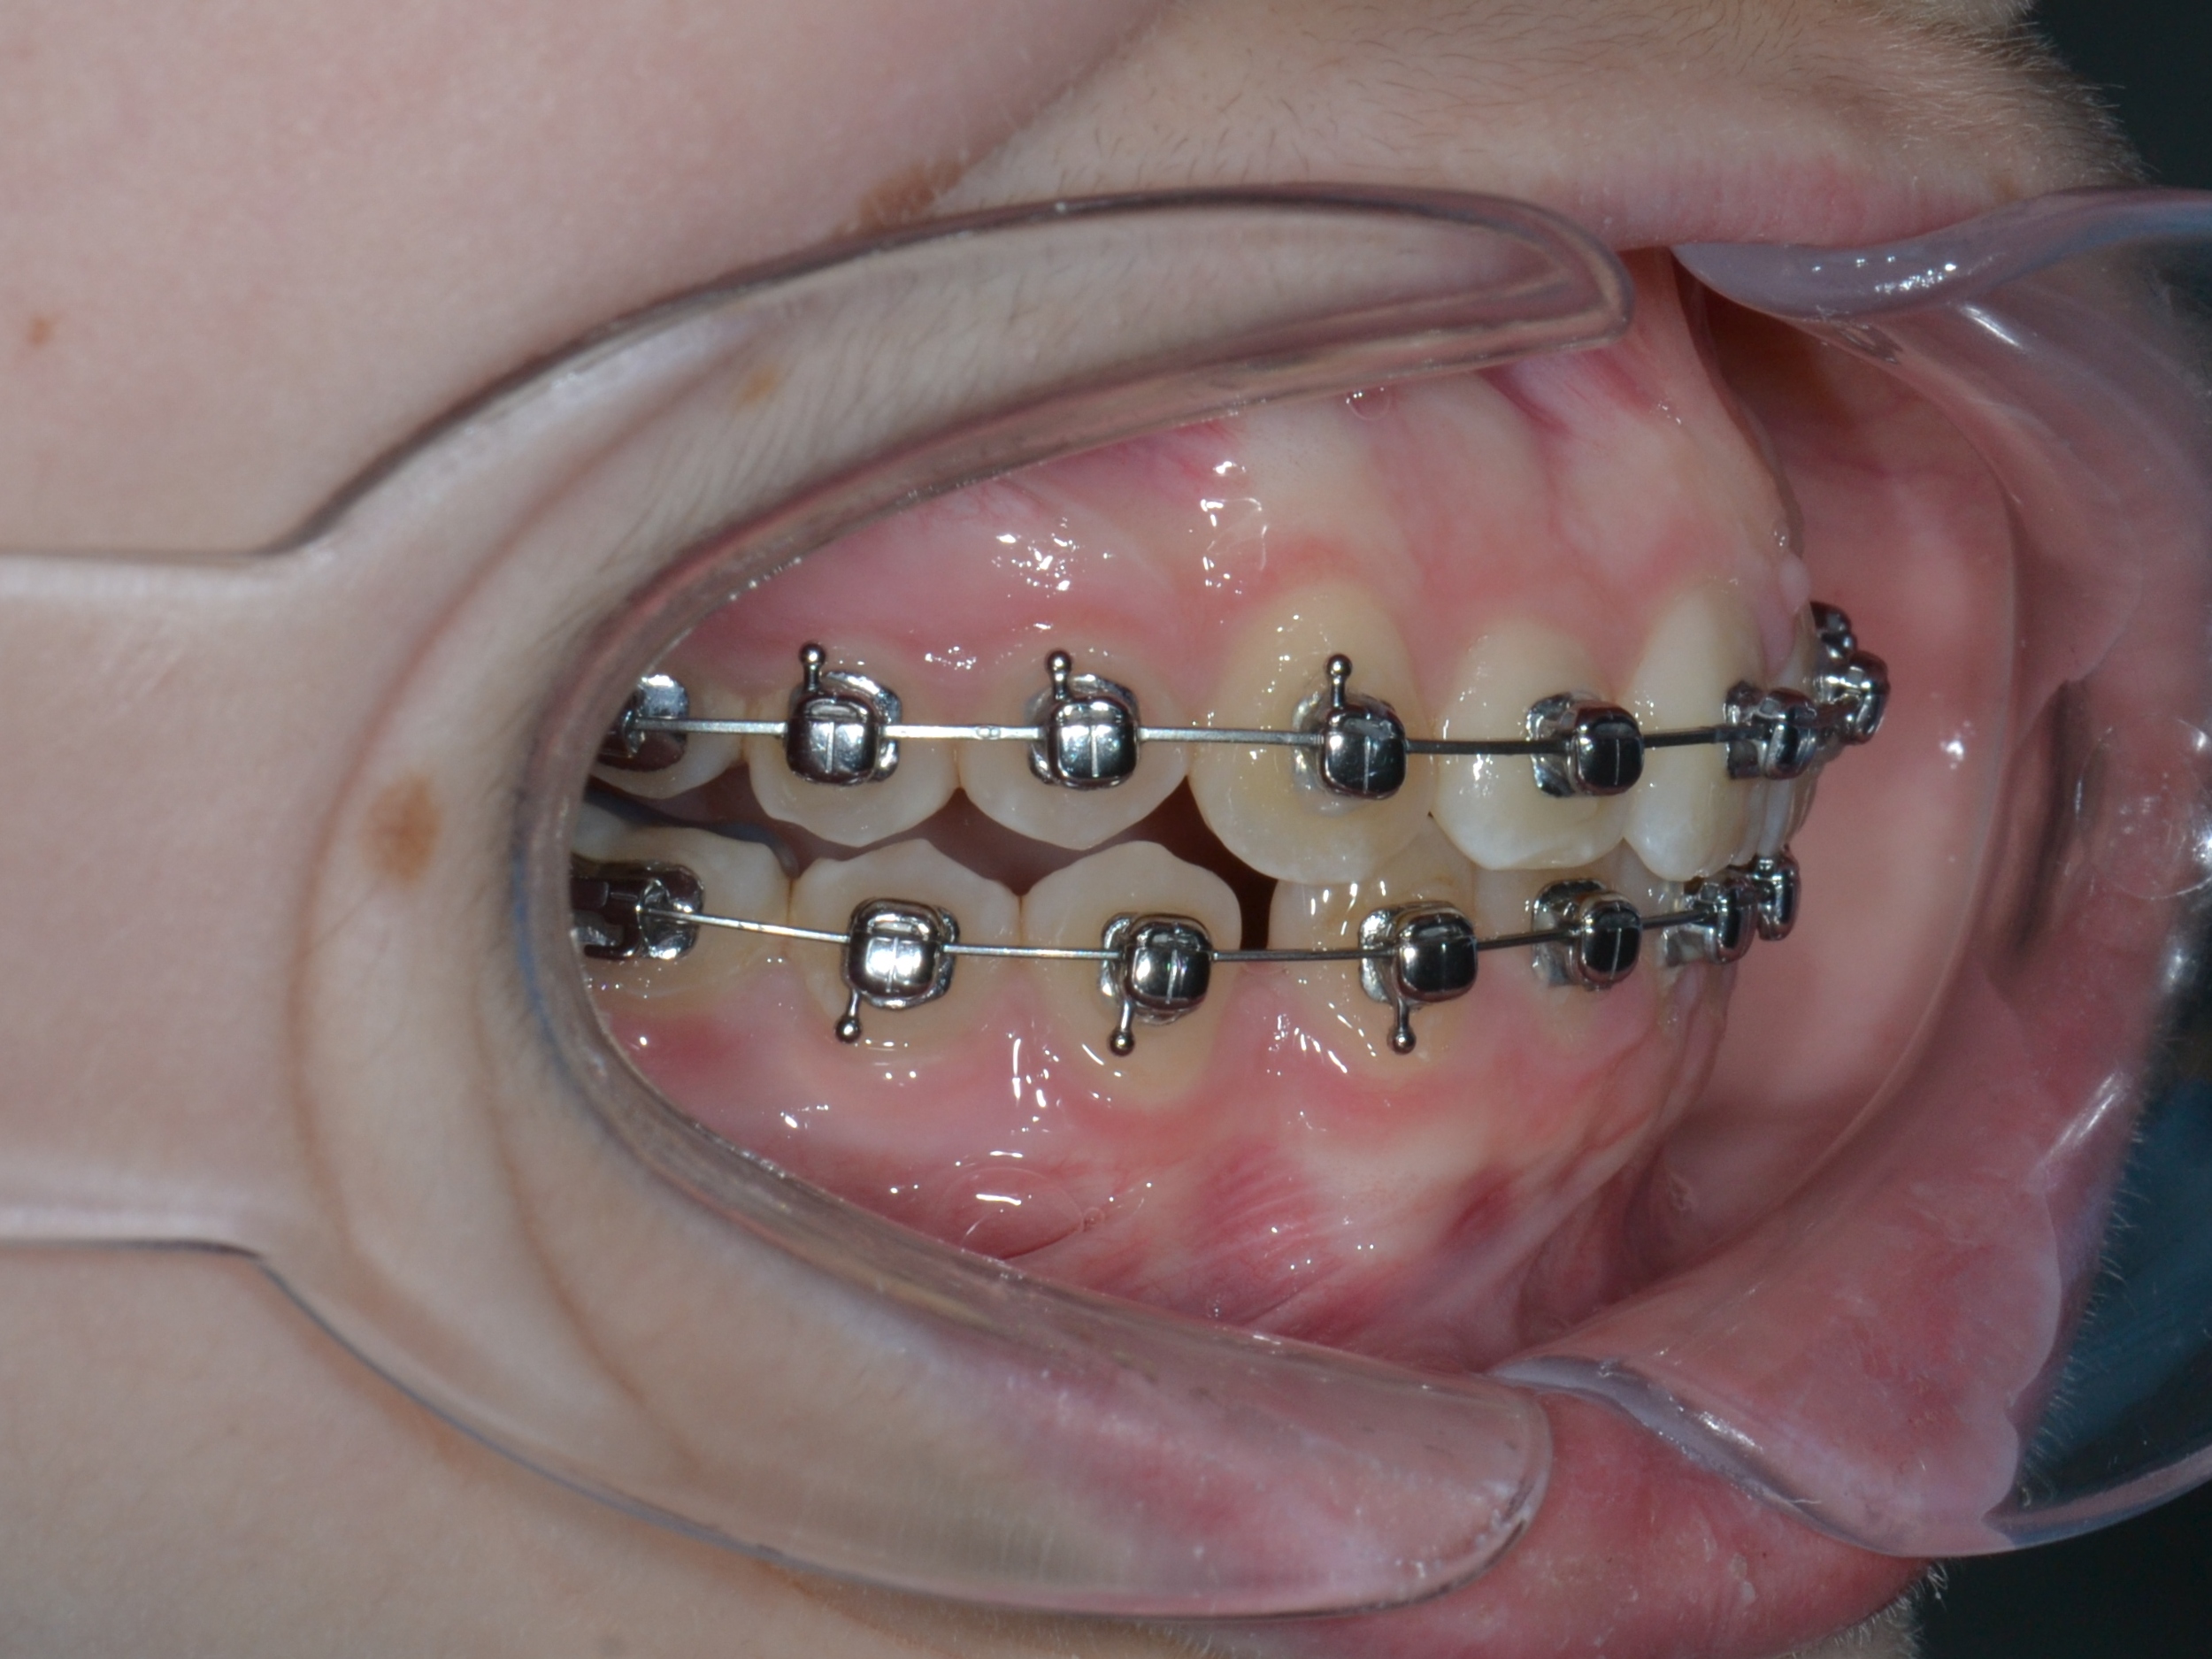

2

6 месяцев

Декабрь 2024 г.